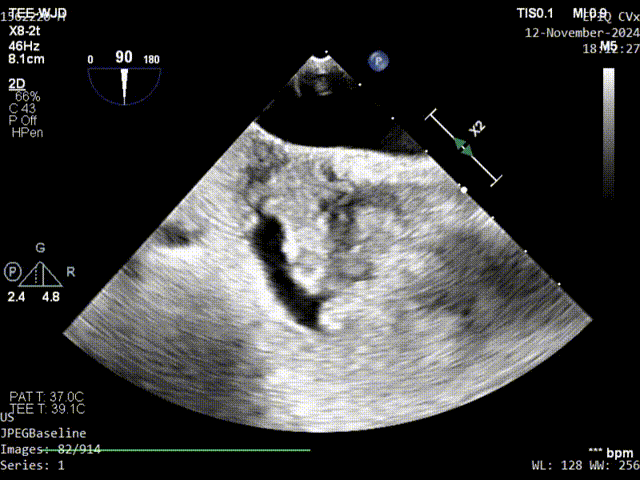

继发隔缝合

原发隔第一针缝合

原发隔第二针缝合

术中通过调整缝线松紧度观察有无右向左分流,确认无分流以后一键完成打结、切线、脱离操作,通过超声确认锁结的位置无移位、形态稳定,无残余分流。

锁前确认

术后即刻